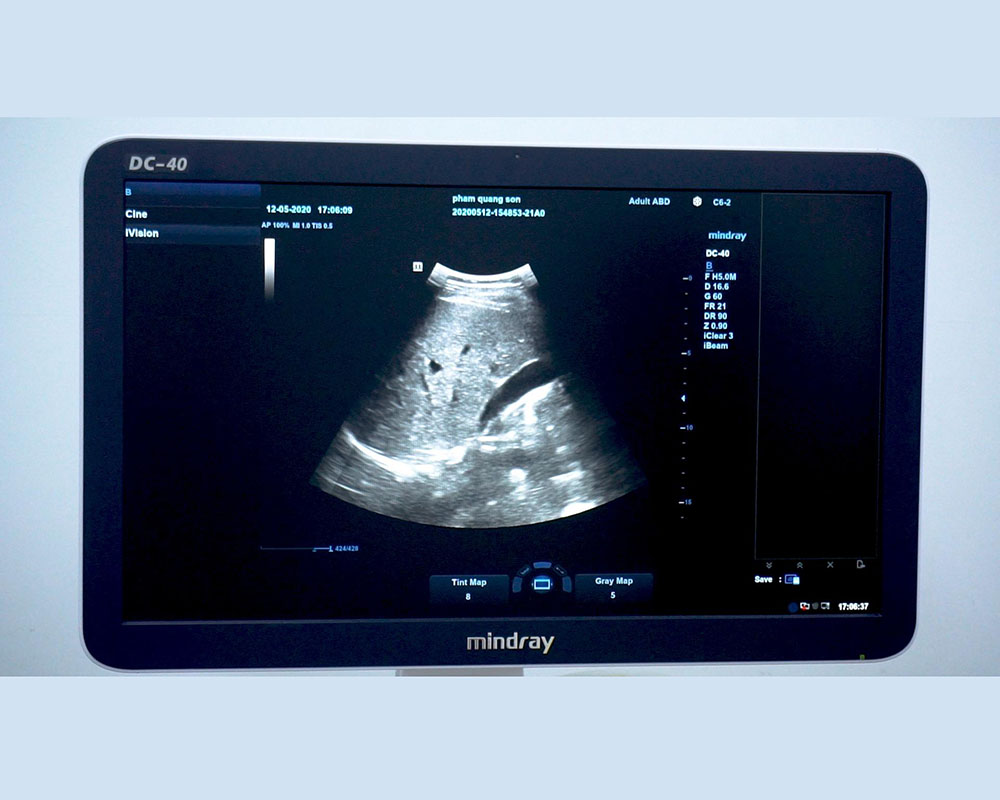

Hình ảnh 2D trên đầu dò Convex C6-2